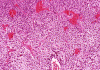

Panel A and B are low-magnification photomicrographs featuring solid sheets of isomorphous, small round to ovoid neoplastic cells with a delicate but rich vascular network. There are also intervening irregular patches of fibrillary neuropils. At high-magnification, the tumor cells appear as fairly uniform round to polygonal cells with perinuclear halo (Panel C). An island of neuropil is present in Panel D. The tumor cells are immunoreactive for synaptophysin (Panel E). The tumor cells were not immunoreactive for neurofilament proteins. At the ultrastructural level, the neoplastic cells contain numerous cell processes filled with vessicles and dense core granules (Panel F and G). Dense core granules and vescicles in high-mangification are shown in Panel H. The vesicles have structures similar to that of the synaptic vesicles, a feature of neuronal differentiation.

Histological, the tumor is composed of solid sheets of small, round to polygonal, isomorphic tumor cells with distinct cell membrane. Within the neoplastic cells is a delicate vascular network. Microcalcifications, when present, are distributed throughout the tumor. The cytoplasm is fine and amphophilic. Perinuclear halo is usually present and prominent, leading to an impression of a clear cell tumor. The summation of these features generates a “honey-comb” pattern similar to that of oligodendroglioma and clear cell ependymoma. The nuclei of neurocytoma are round, small, and contain fine and speckled chromatin. Nucleoli are indistinct. Mitotic figures are not readily seen or infrequent. Irregular and small islands of neuropils are present. Perivascular arrangement of neuropils in some areas may closely mimic the coronary perivascular fibrillary hypocellular mantles (perivascular pseudorosettes) that are considered evidence of ependymoma. The real ependymal pseudorosettes are more orderly and fibrillary. A high index of suspicion is important to avoid this trap.